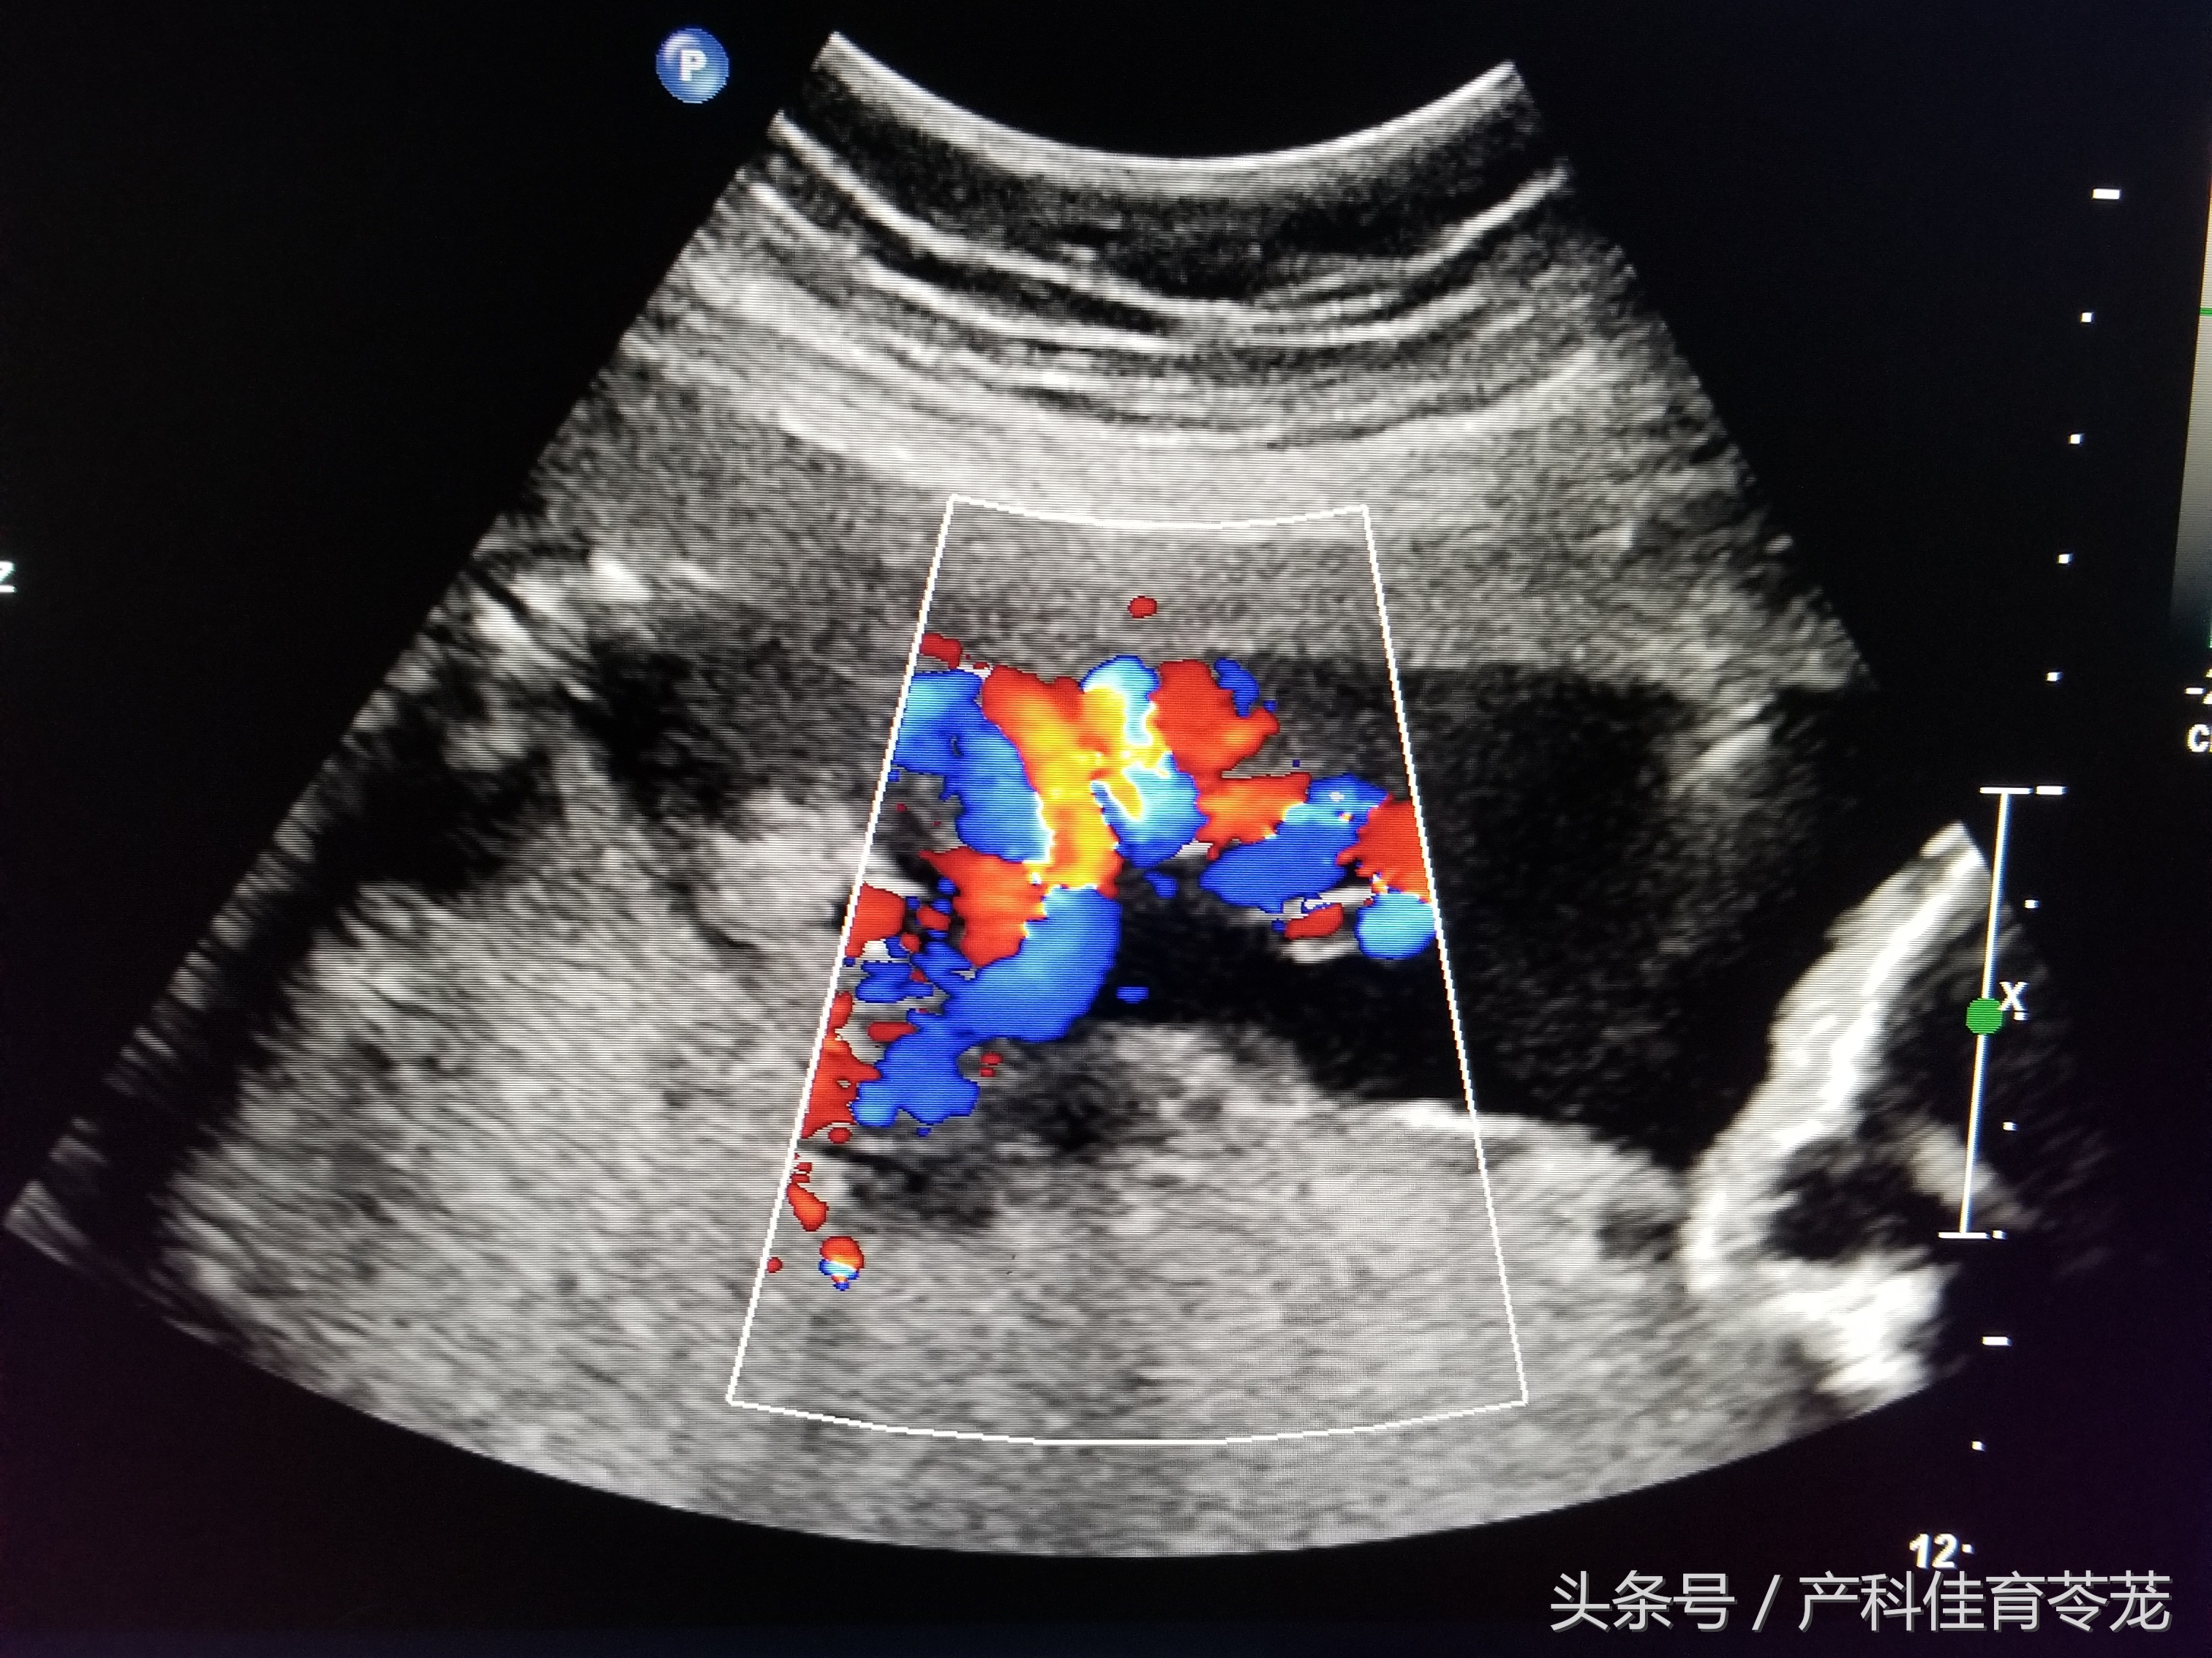

六、胎儿脐动脉血流

在妊娠中晚期,可以用脐动脉的多普勒血流参数来评估胎盘循环,判断是否存在胎儿发育迟缓、判断是否存在胎儿缺氧。另外,胎儿如果有染色体异常、先天畸形等,脐血流有时也会表现出异常。

一般来说,B超会告诉您下列三个值:

PI——博动指数;

RI——脐动脉血流阻力指数;

S/D——脐动脉血流速度峰谷比。

数值多少与怀孕的周数有关,妊娠28周以后,S/D大于3.0或者RI大于0.6表示血流阻力加大,血液速度变慢,胎盘供血受限 ,胎儿有可能缺氧了。

注意:根据脐血流判断胎儿是否异常不是那么简单,还需要根据其他指标来综合判断,单纯的S/D高于正常不要过于恐慌,不一定代表异常。